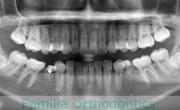

歯並びをきれいにしたいということで来院されました。非常に強い前歯の突出と叢生(でこぼこ)でした。上下左右から小臼歯を抜歯してマルチブラケット法にて治療を行いました。前歯の歯根が短く、歯根吸収のリスクが非常に高いケースでした。前歯に負担をかけないように3年弱、30回程度の通院で治療を行いました。

- ≫治療前